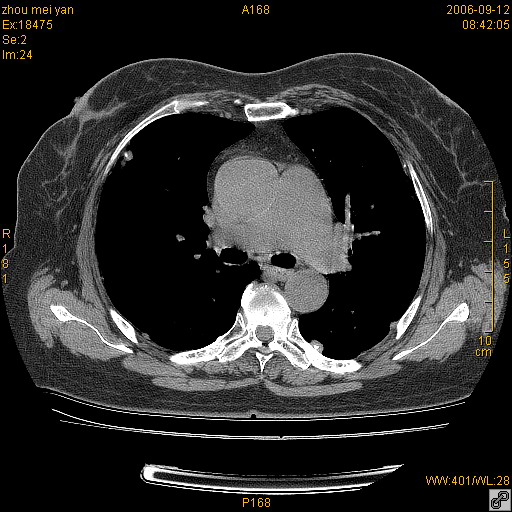

患者、女、55岁。因心率失常住院检查ct发现胸部多发结节。腹部b超肝、胆、胰、脾、肾、子宫附件未见异常。无结核病史,无粉尘接触史。请大家来会诊。谢谢!

病变位于胸膜,多发结节,边界清楚,内见小结节状钙化。其它未见异常。

双侧胸膜多发结节,形态不规则,边缘较清楚,每一个结节中心似乎都有钙化点的特征,与胸膜广基相切。临床无结核病史,无粉尘接触史。

胸膜间皮瘤可能性大。在气管隆突前可见一肿大淋巴结影。

影像表现十分有特点:双侧肋胸膜及膈胸膜广泛散在分布大小在2至6mm左右,较大病灶中心可见钙化。

考虑恶性胸膜间皮瘤可能性大,病灶位于胸膜,以宽基地与胸膜相连,呈结节样改变,部分病灶内可见点状钙化影。请各位老师多多指导!

双侧肋胸膜及膈胸膜广泛散在分布大小不等结节影,较大病灶中心可见钙化。